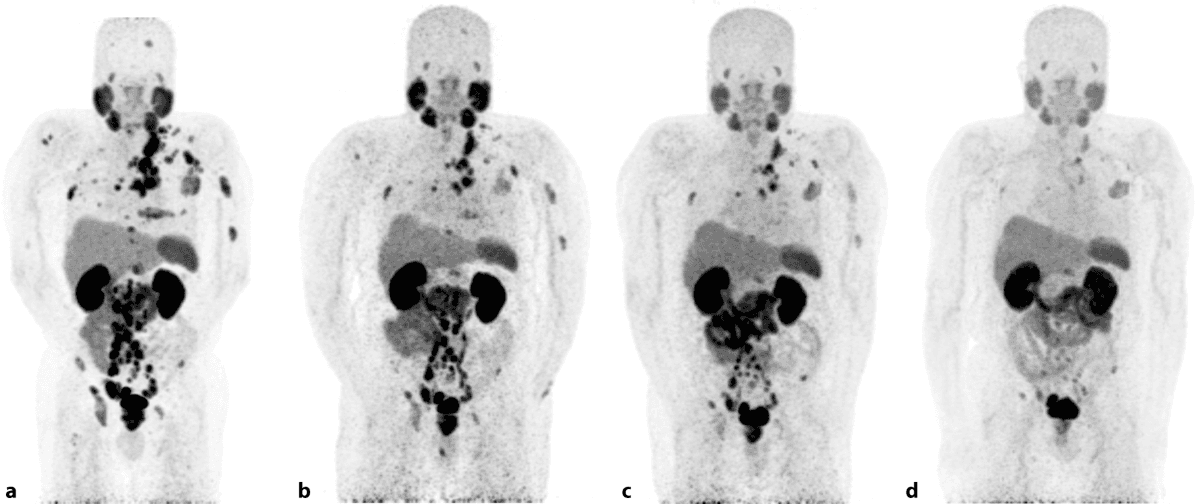

Lutetium treatment of prostate cancer